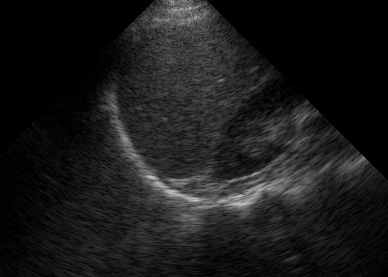

One common pitfall is mistaking the gallbladder for free fluid, which can happen if you scan too anteriorly.

(Figure 25/25.1)